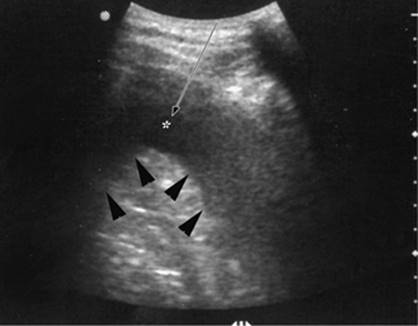

000193

Figure 35.6. Ultrasound image showing typical appearance for thoracentesis guidance. The central target (pleural effusion) is identified by an asterisk, lung margin by arrowheads, and drainage catheter pathway with an arrow.